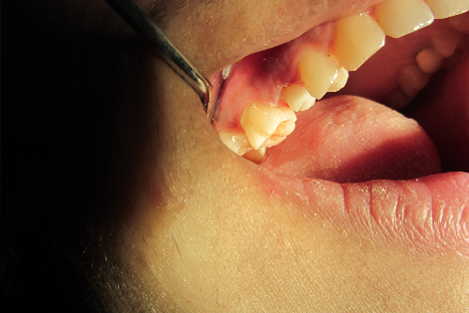

Post n Core